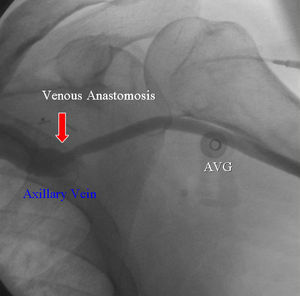

Pacientes y MétodosEntre enero de 2005 y marzo de 2006, nueve pacientes se sometieron al procedimiento descrito. En todos ellos se implantó un injerto arteriovenoso usando la vena axilar infraclavicular como receptora del flujo de salida (fig. 1). La anastomosis arterial se llevó a cabo en la arteria axilar o la humeral. La vena axilar se expuso mediante la separación de las fibras del pectoral mayor medial al pectoral menor. El injerto se tunelizó subcutáneamente a través de las fibras musculares del pectoral mayor. Todas las anastomosis se crearon en el lado homolateral del cuerpo. Efectuó los procedimientos un cirujano vascular en dos hospitales comunitarios.